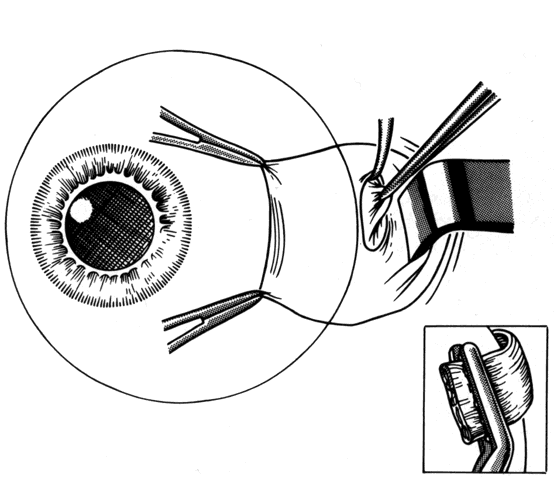

The incision should provide sufficient exposure and should be one the surgeon feels comfortable using. Our preference is to attempt to use a cul-de-sac incision whenever possible. This incision eliminates dissection through conjunctiva and anterior Tenon's capsule. When corrections require surgery on the superior rectus, conjunctiva is preserved for the remote possibility that a glaucoma filtering procedure may be required in the future (Figs. 13 and 14). The conjunctival incision can usually be made either through the old incision or just posterior to it.

Fig. 13. Incision is made through the conjunctiva. Conjunctiva is then dissected free from any adherent Tenon's capsule that overlies the site of the old muscle insertion. A blunt-tip Wescott scissors facilitates this dissection.

Fig. 14. This dissection is carried past the insertion until a hook is able to be passed under the muscle without restriction.